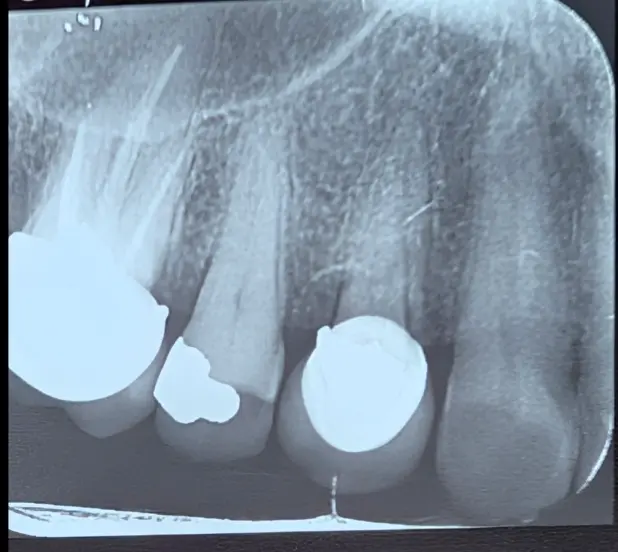

در این کیس، بیمار با شکایت از درد شدید سمت راست فک بالا مراجعه کرد. بیمار و حتی نمای ظاهری دندانها (سایش شدید دندان ۵) انگشت اتهام را به سمت دندان پرمولر دوم میبردند، اما حقیقت چیز دیگری بود.

نتایج تستها نشان داد که دندان ۵ با وجود سایش، مشکل پالپی ندارد و عامل اصلی درد، دندان ۴ است که بهتازگی روکش شده.

نکته کلیدی: در دردهای شدید، پدیده "درد ارجاعی" میتواند هم بیمار و هم دندانپزشک را گمراه کند. تنها تستهای دقیق اندو میتواند مجرم واقعی را از دندانهای کناری تمیز دهد.